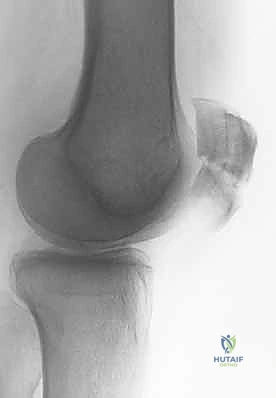

الأشعة السينية (X-rays): هي الخطوة الأولى والأساسية. يتم أخذ صور من زوايا متعددة:

- المنظر الأمامي الخلفي (AP View): لتقييم النمط العام للكسر.

- المنظر الجانبي (Lateral View): حاسم جداً لتقييم مدى تباعد أجزاء الكسر (Displacement) وعدم انتظام السطح المفصلي (Articular step-off).

- منظر السماء (Skyline View): مفيد لرؤية الكسور الطولية وتقييم التمفصل بين الرضفة وعظم الفخذ، ويتم إجراؤه إذا كانت حالة المريض تسمح بثني الركبة قليلاً.